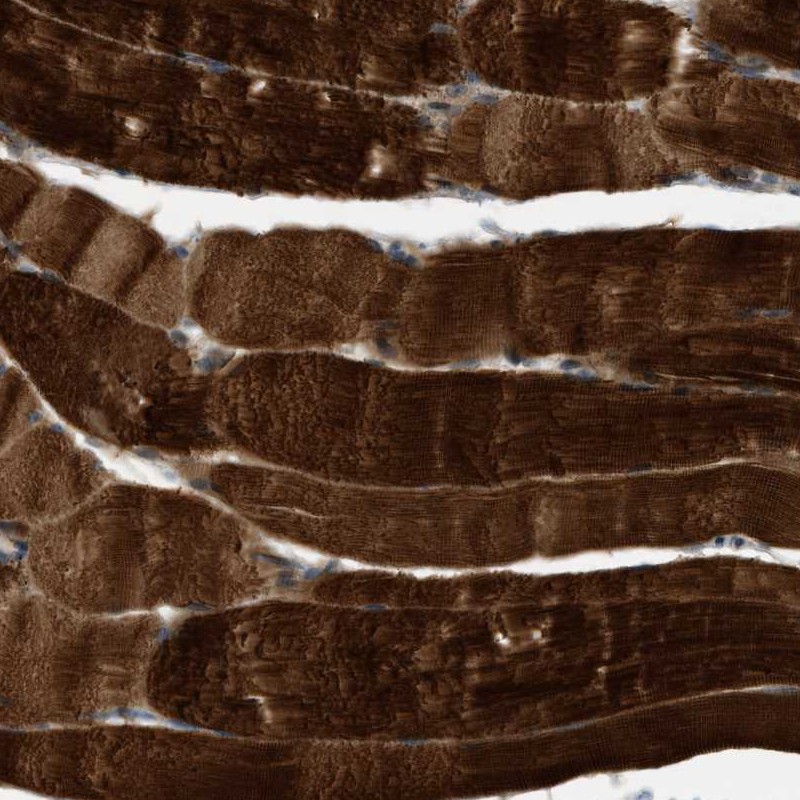

Immunohistochemical staining of human skeletal muscle shows strong cytoplasmic positivity in myocytes.